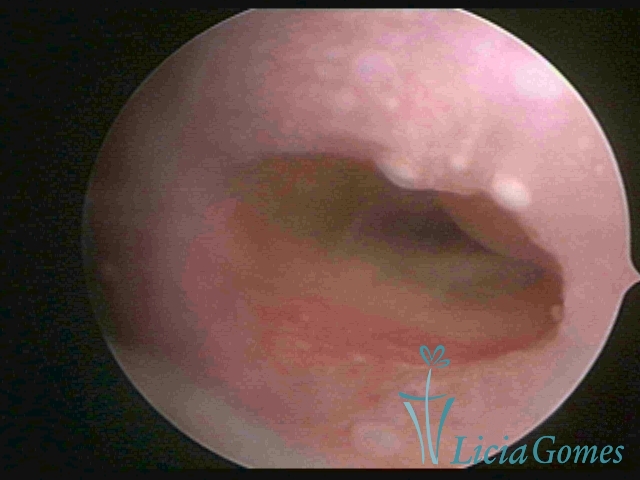

Segunda porção ou setor médio

No terço ou setor médio do canal cervical perdemos o detalhe das papilas, sendo possível a visualização de pregas e criptas. Normalmente observamos os sulcos longitudinais, que são os tecidos mais compactos, com a superfície mais vascularizada, cujos vasos seguem o seu trajeto.